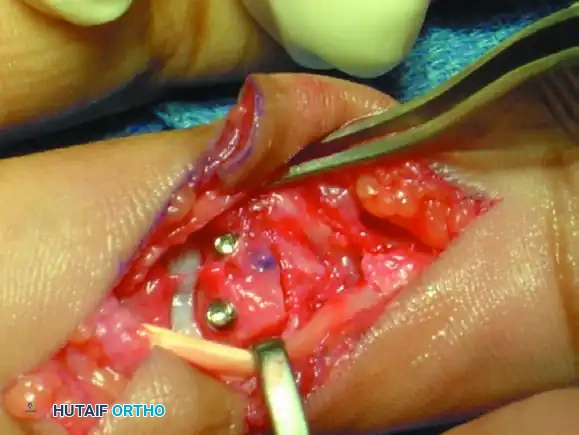

Figure 67-49B: Volar exposure of the middle phalangeal base and geometrical preparation of the defect to receive the graft.

Figure 67-49D: Fixation of the hemi-hamate graft with two minifragment screws to replicate the middle phalangeal base concavity.

- Volar Approach: A volar Bruner or midlateral incision is made to approach the PIP joint. The flexor tendon sheath is opened, and the A3 pulley is released. The flexor tendons are retracted laterally.

- Joint Exposure ("Shotgunning"): The volar plate is released distally. The collateral ligaments are sharply released from their proximal attachments to allow the joint to be hyperextended or "shotgunned." This provides unparalleled visualization of the articular defect on the middle phalanx.